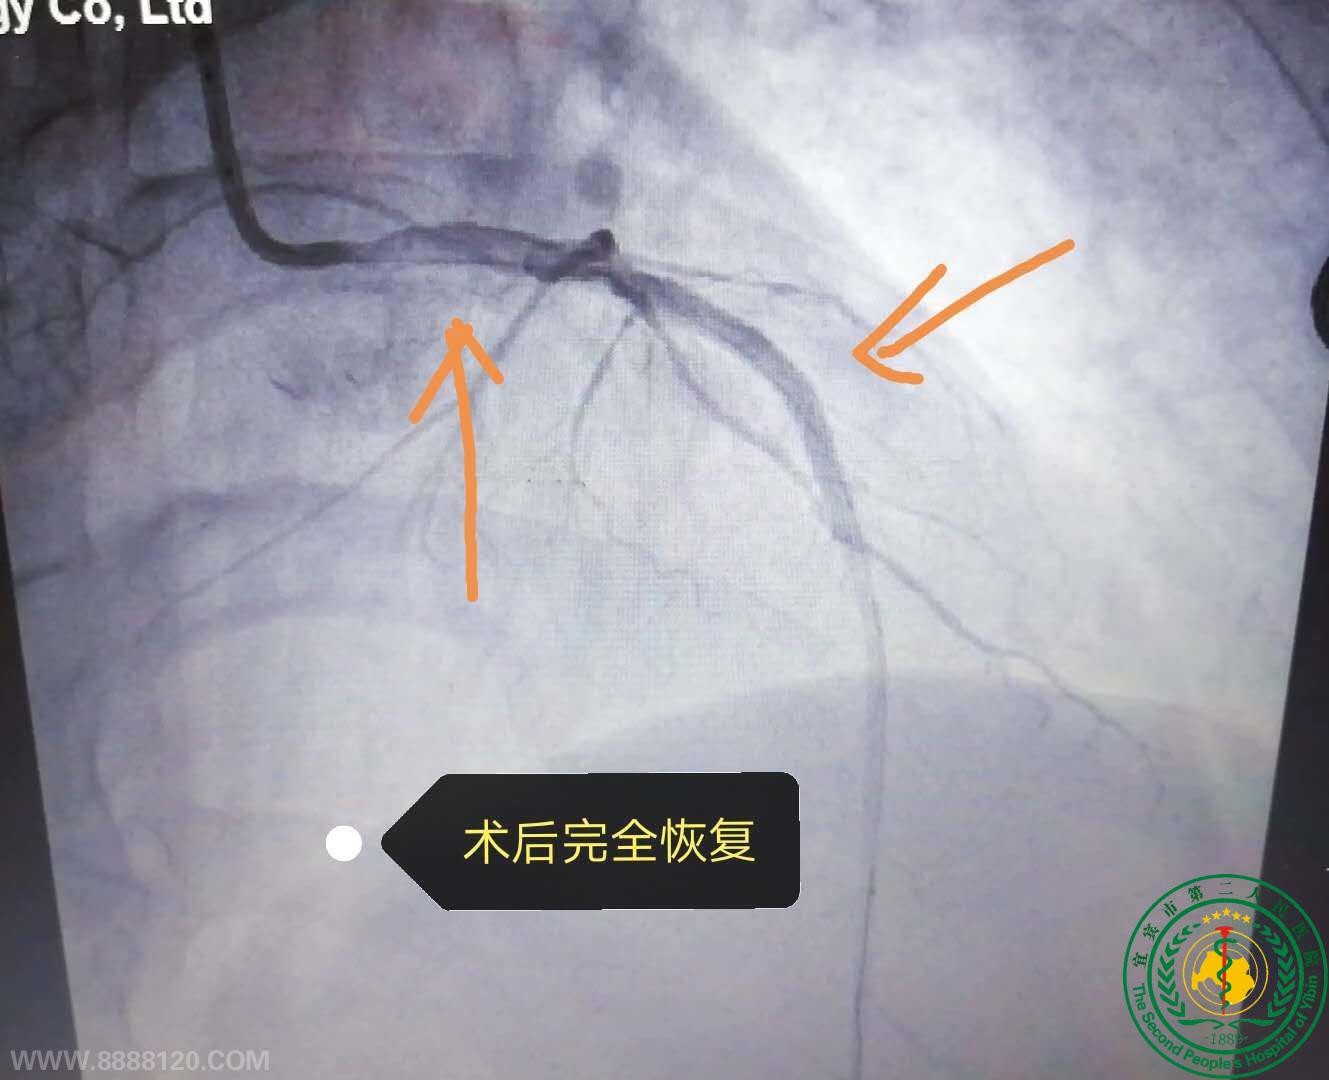

心内一科成功为一名高危左主干病变患者施行介入治疗

心内一科成功为一名高危左主干病变患者施行介入治疗17027